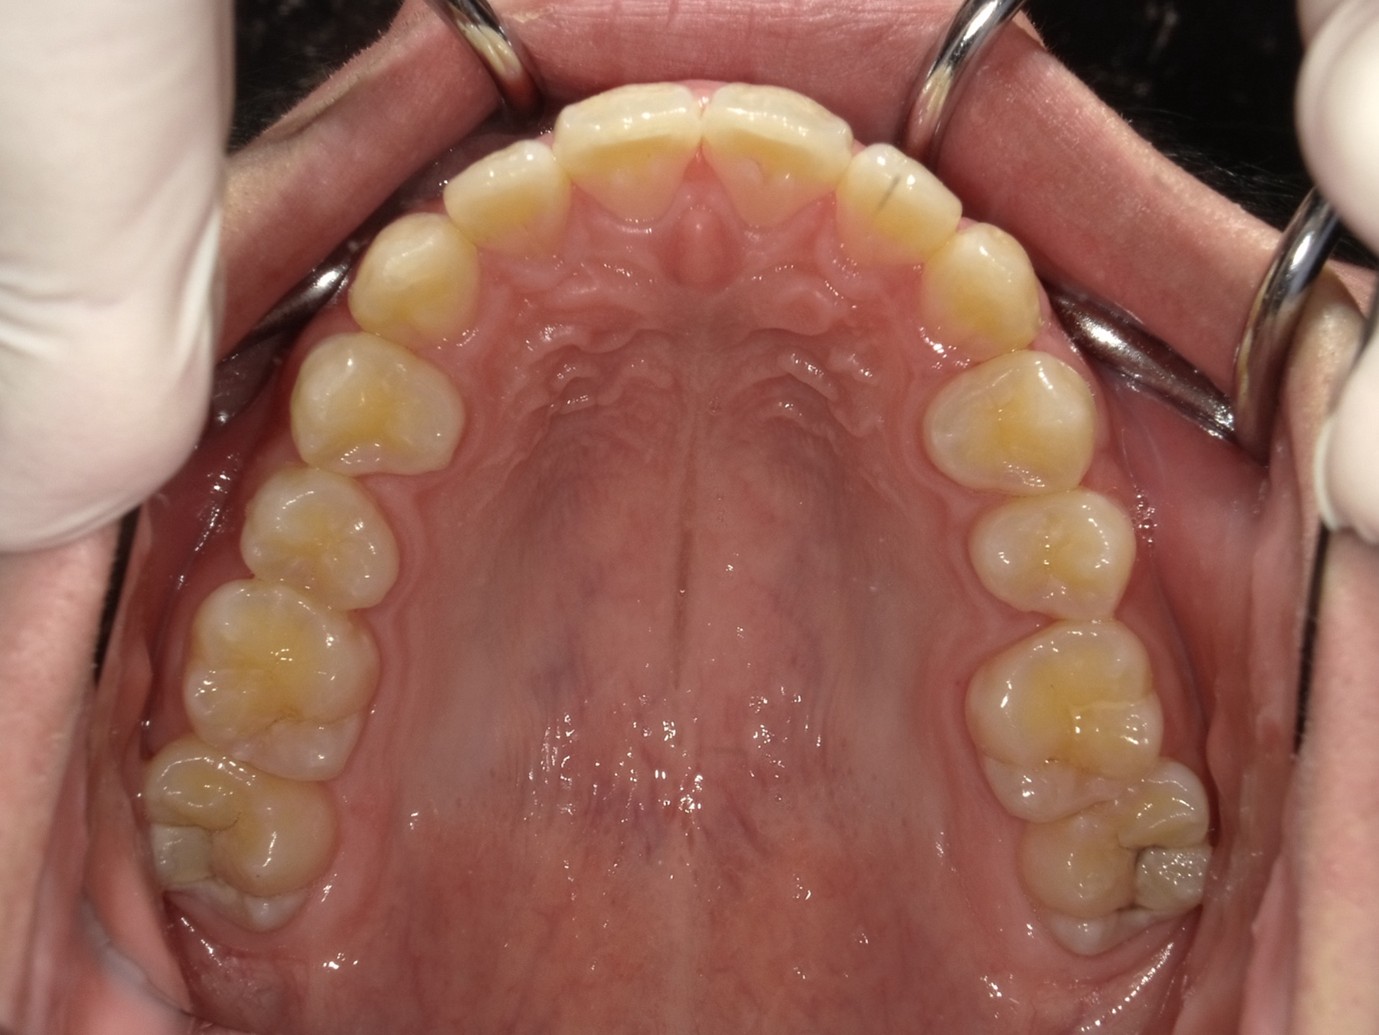

| 症例分類 | 過蓋咬合 |

|---|---|

| 主訴 | 他の歯科医院で咬み合わせを指摘された |

| 年齢 | 10歳10ヶ月 |

| 性別 | 男性 |

| 抜歯部位 | なし |

| 使用装置 | 拡大装置、咬合斜面板(取り外し式の矯正装置) |

| 治療期間 | 3年4ヶ月 |

| 保定装置 | 咬合斜面板 |

| 費用 | 相談料0円、検査料55,000円 動的矯正治療費330,000円 調整料6,600円×30回分 保定装置料0円 |

| リスク・注意点 | 上の顎の大きさに対して下の顎が小さく、過蓋咬合が生じています。これらを改善するために、幅の狭搾している歯列を側方に拡大したのち、下顎の成長を促進しました。

歯の動き方には個人差があり、予想された治療期間が延長する可能性があります。 治療中は矯正歯科装置が歯の表面に付いており、歯が磨きにくくなるため、むし歯や歯周病が生じるリスクが高まります。ハミガキを適切に行ってお口の中を常に清潔に保ち、さらに、かかりつけ歯科医に定期的に受診することが大切です。 矯正歯科装置の使用状況、定期的な通院など、矯正歯科治療には患者さんの協力が必要であり、それらが治療結果や治療期間に影響します。 治療の経過によっては当初予定していた治療計画を変更する可能性があります。保定装置の装着時間が十分確保できない場合、歯並びや、咬み合せの「後戻り」が生じる可能性があります。 上下両側第二大臼歯の萌出を観察する必要があります。(治療後の写真は成人矯正開始直前の資料です。) |